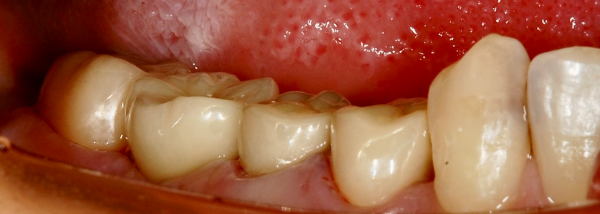

部分矯正は2〜3ヶ月で予定の位置まで歯を起こすことができました。保定期間を待った後、インプラント上部も含めて、4本全てに補綴物を作成しました。

治療後の様子

完成時の写真がこちらになります。

患者様は、今までは右で噛みにくく自然と左ばかりで噛んでいたが、今はバランス良く噛めますとおっしゃってくださいました。